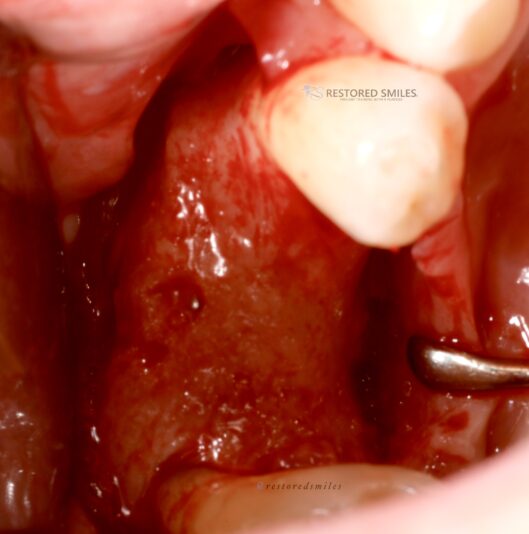

• I’m a big fan of placing immediate implants when indicated. However, with this full arch case this patient had extreme buccal and facial undercuts which prevented immediate implant placement. 6cc’s of bone were used to graft a fair amount of the upper right and upper left quadrant using CGF protocols. 5 to 6 months later we have beautiful,…

Read more